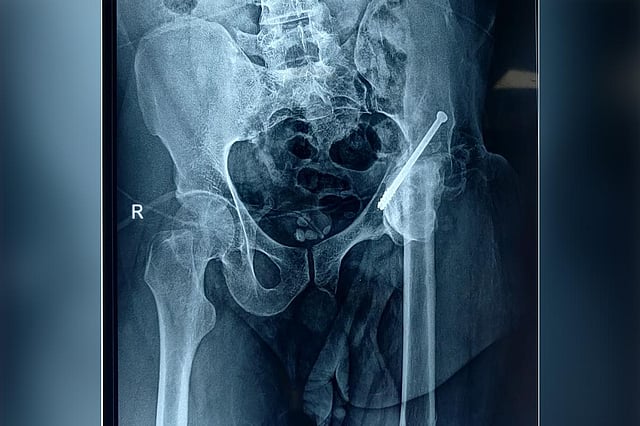

An X-ray of Kasim

Kasim was referred to Aster RV Hospital, JP Nagar, Bengaluru by his friend. After a thorough evaluation and understanding of his requirements and the gravity of his injuries, the doctors at the hospital decided to carry out an advanced surgery. Accordingly, a complex primary hip reconstruction surgery was conducted on February 2 using specialized hip implants since there was extensive damage to his hip.

The doctors used 3D printing technology to get a three-dimensional view of the injured area. 3D printing allows the surgeon to get a physical 3D model of the desired patient anatomy that could be used to accurately plan the surgical approach along with cross-sectional imaging or modelling custom prosthetics.

Eventually, the technology helped the doctors map out the best way to approach the damaged area. “Kasim had lost the entire ball and socket of his hip and the remnant was fixed to his hip due to which no movement was possible. The repeated surgeries and loss of soft tissue changes the normal anatomy which made the surgery more difficult,” explained Dr JV Srinivas, Lead Consultant – Orthopedics, Aster RV Hospital.